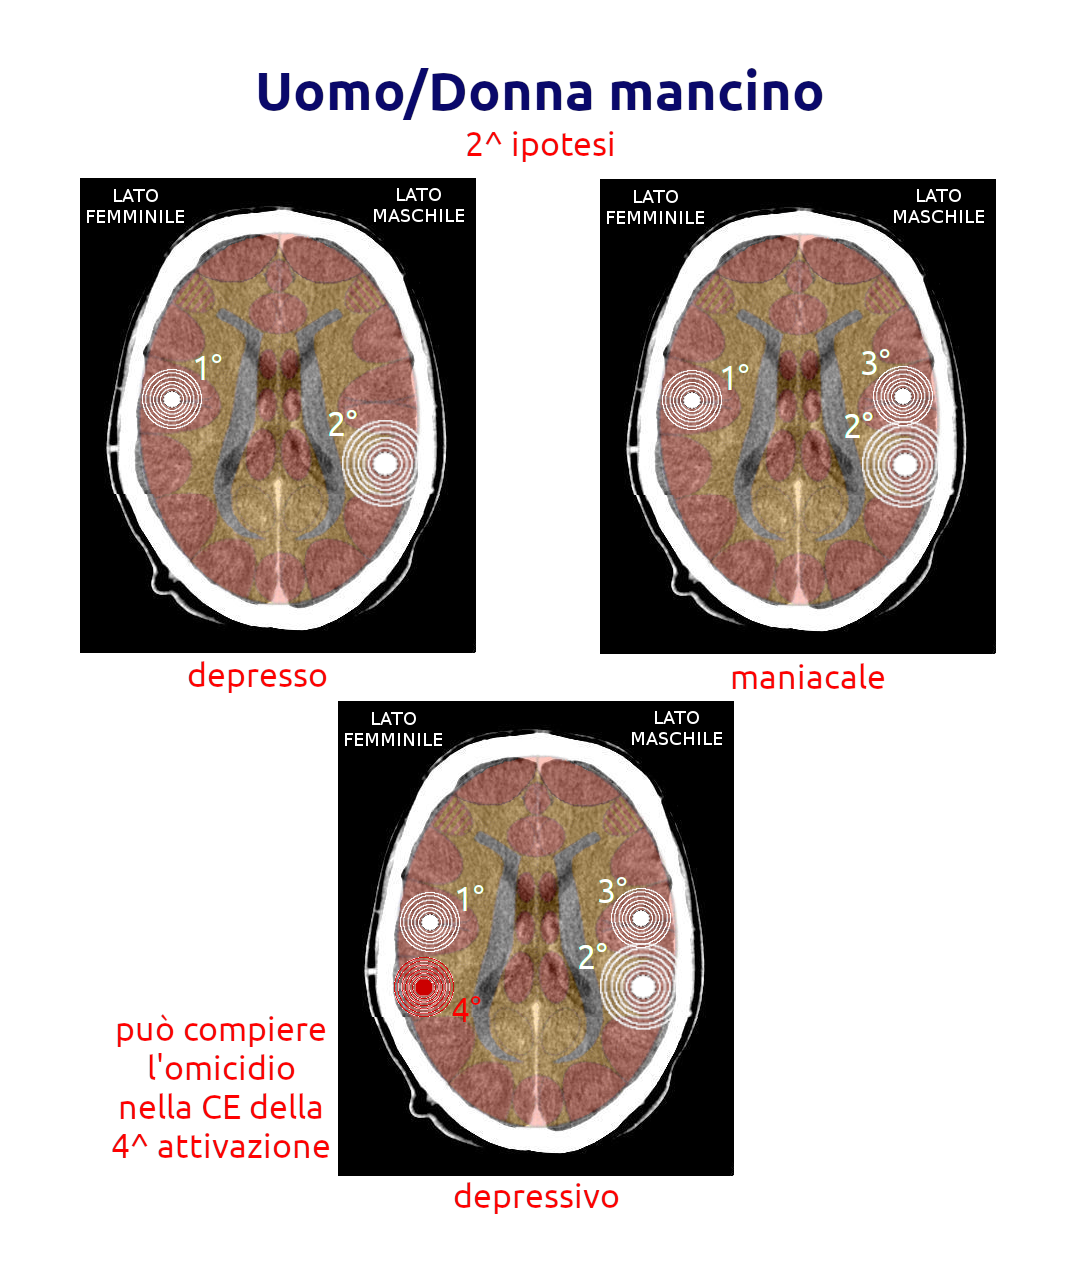

5.3.4.2 Uomini e donne mancini

- Quando la persona è maniacale, il terzo SBS impatta l'emisfero destro e lo porta in depressione

- Quando la persona è in depressione, il terzo SBS impatta l'emisfero sinistro e lo porta alla maniacalità

Interessante è osservare la possibile evoluzione dell'individuo verso questa compulsione, ma occorre tenere conto della lateralità e della condizione al momento del terzo impatto sulla corteccia insulare:

- In questo caso (ipotizzando che si tratti di un maschio) la persona era in fase maniacale, protestava e forse minacciava, forse era anche arrivato a vie di fatto ma riusciva a contenersi. Poi all'ennesimo evento che coinvolge il quarto dei relè (quello della rabbia), sembra calmarsi, sembra spento o "a bada" (la quiete prima della tragedia), ma quando quest'ultimo SBS trova una soluzione, al momento della crisi epilettoide scatta la furia omicida e compie il delitto. La sua maniacalità residua potrebbe indurlo a scappare o a non provare alcun rimorso. Questa è solamente una ipotesi!

- In questo caso (ipotizzando che si tratti di un maschio) su una condizione depressiva di un certo rilievo ("Era un uomo così mite, quasi dimesso!") si attiva il quarto SBS importante che spedisce l'individuo in fase maniacale ed è qui che potrebbe compiere l'omicidio (a caldo). Compiuto il misfatto potrebbe ripiombare in una forte depressione, lasciandosi catturare senza opporre resistenza. Questa è solamente una ipotesi!

- In questo caso (ipotizzando che si tratti di un maschio) sembra ripetersi il meccanismo descritto al punto precedente. Questa è solamente una ipotesi!

- In questo caso (ipotizzando che si tratti di un maschio) sembra ripetersi il meccanismo descritto al primo punto. Questa è solamente una ipotesi!